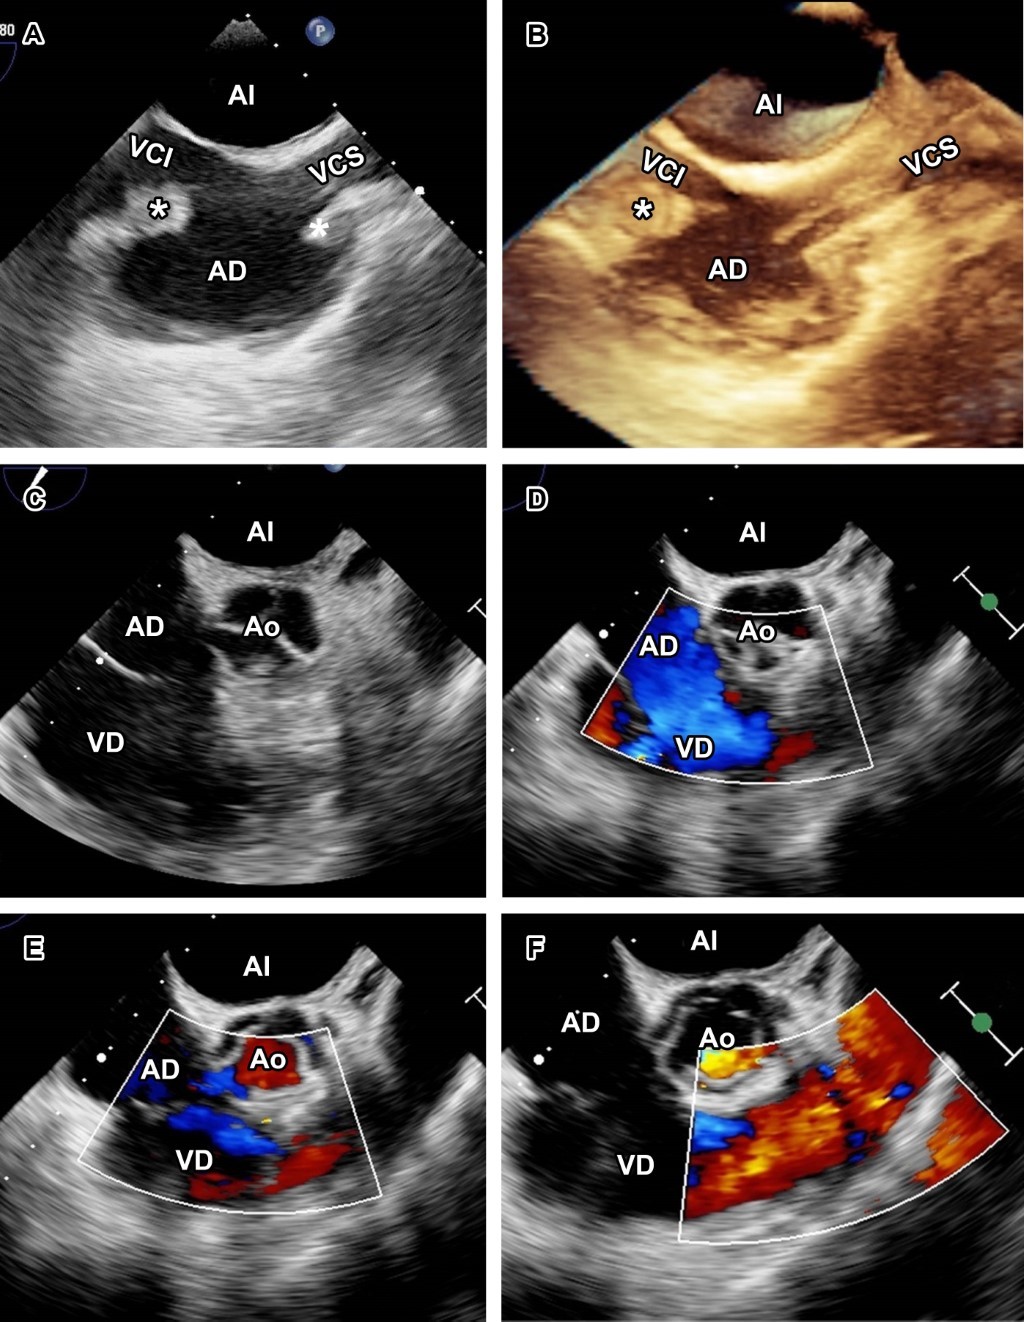

A la exploración física, ruidos cardiacos y respiratorios se auscultaron sin alteraciones. Laboratorios solo reportaron anemia (hemoglobina 8.7 g/dL). Ante sospecha de EI se tomaron hemocultivos y se inició tratamiento con vancomicina más ceftazidima. El ecocardiograma transtorácico (ECOTT) con mala ventana acústica mostró catéter de hemodiálisis engrosado con vegetación en la aurícula derecha (Figura 1), y se realizó ecocardiograma transesofágico (ECOTE), observándose vegetación en el catéter de hemodiálisis así como en aurícula derecha y sin compromiso valvular (Figura 2).

Figura 1